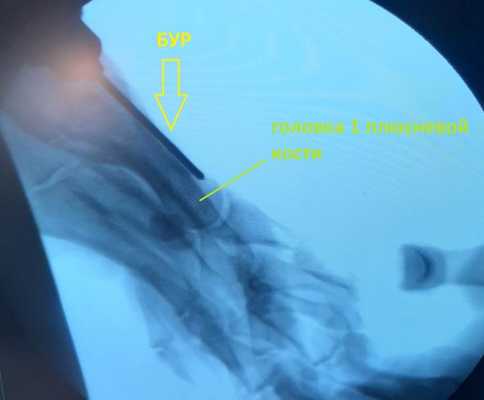

Операция по удалению «косточки» чаще всего длится не более 1 часа, если речь идёт только об 1 пальце стопы, но продолжительность операции будет зависеть от степени деформации. Сцществует много вариантов хирургического лечения «косточки», как с применением открытых методик так и чрескожных. При выполнении операции закрытым способом чаще всего требуется создать искусственный «перелом» который хирурги называют "остеотомия", для того, чтобы восстановить нормальное положение костей стопы. При выполнении открытой операции по внутренней поврехности стопы делается разрез длиной 5-7 см, что обеспечивает прекрасную визуализацию, позволяющую точно определить необходимый угол опила и степень смещения фрагментов кости. При достаточном опыте хирурга возможно выполнение остеотомии закрытым способом при помощи бура из 5 мм разреза, контроль опила при этом осуществляется при помощи рентгена, но решающее значение имеют тактильные ощущения хирурга.

При миниинвазивных вмешательствах не остаётся больших послеоперационных рубцов, и уровень болей после операции как правило ниже, но чаще встречаются такие проблемы как неполная коррекция деформации, замедленная консолидация остеотомий.

Возможно и сочетание закрытых иоткрытых методов, когда вмешательство на 1 плюсневой кости выполняется открыто, а на малых лучах и фалангах закрыто, при помощи бура.